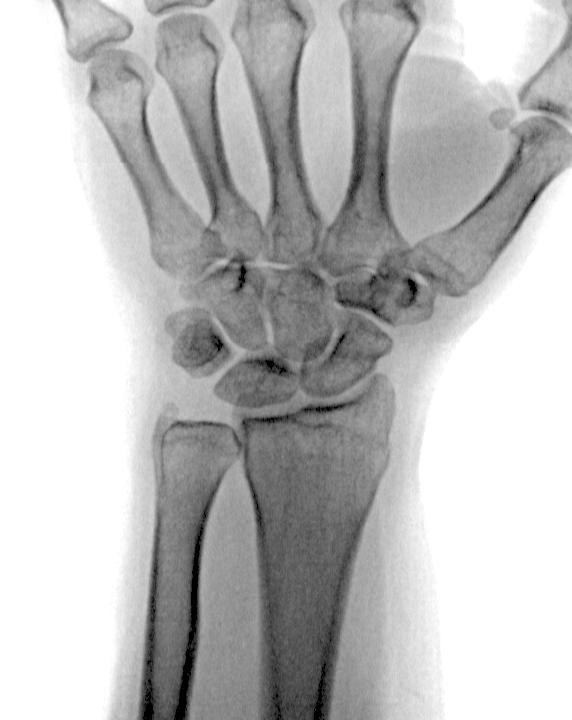

Молодой мужчина. Травма (кто не ленив, может легко найти её последствия). И случайная находка. Что заключить: киста? липома? Что б веселее думалось, немного информации https://radiomed.ru/forum/...

Женщина 1956г.р., упала с высоты собственного роста. Ести ли перелом луча?

77. Костный возраст

Здравствуйте. Помогите, пожалуйста, определить костный возраст. Ребенку 3 года 2 месяца сзадержкой роста, обследование только начали.

Девочка, 8 лет. Диагноз ППР. Какому костному возрасту соответствует снимок? Открыты ли точки роста?